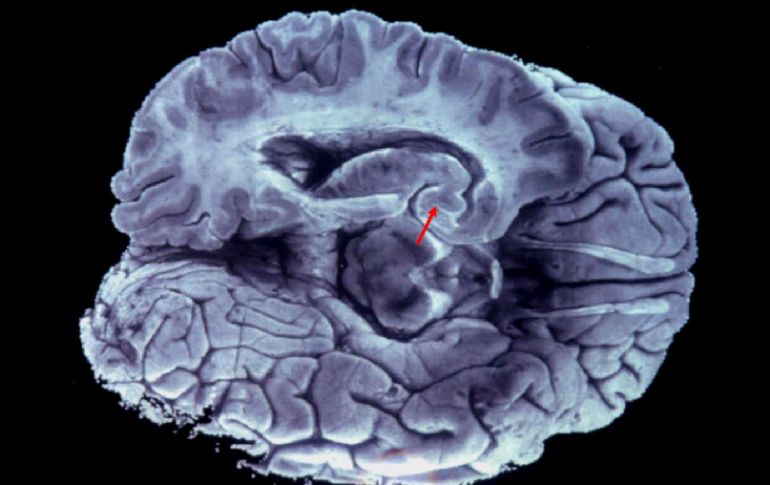

Suplementos | Se pierden entre 0.1 y 0.3 de volumen cerebral por año a partir de los 20 años de edad Descubren disminución del cerebro a causa de enfermedades Se pierden entre 0.1 y 0.3 de volumen cerebral por año a partir de los 20 años de edad Por: SUN 12 de abril de 2014 - 13:09 hs La EM es un mal del sistema nervioso central que afecta a más de 20 mil personas en México. ARCHIVO / CIUDAD DE MÉXICO (12/ABR/2014).- Una persona pierden entre 0.1 y 0.3 de volumen cerebral por año a partir de los 20 años de edad, pero en los pacientes con padecimientos neurológicos se ha demostrado que este porcentaje es mayor y variable. "Una de las enfermedades que cursan con mayor cantidad de atrofia es el Alzheimer, el cual puede presentar una pérdida del 6 al 20 por ciento de su tamaño al año, mientras que un paciente con esclerosis múltiple pierde de 1.6 hasta 3.4 por ciento en el mismo lapso, cifras variables en los diferentes estudios", refiere la doctora Miriam Jiménez González, gerente médico de Neurociencias de Novartis México. Esta pérdida de tejido cerebral se refleja en el grado de discapacidad del paciente, ya sea motora o cognitiva. Gracias a la incorporación de la resonancia magnética a los estudios de imagen que se hacen a los pacientes con enfermedades neurológicas como la esclerosis múltiple, el Alzheimer o el Mal de Parkinson, se ha podido identificar las lesiones clásicas de estos padecimientos. Miden pérdida cerebral Cada vez está cobrando mayor importancia la técnica de volumetría cerebral, con la que se puede detectar a tiempo el nivel de pérdida de tejido y suministrar, de manera oportuna, la mejor terapia para el paciente, dice Jiménez. Para conocer el tamaño de la masa cerebral es importante mencionar el papel de la resonancia magnética que desde hace cinco años ha tomado mayor relevancia y que se suma a la imagenología de radiación ionizante (rayos x y tomografía axial computada) para valorar este deterioro, refiere el doctor Erick Pasaye Alcaraz, doctor en ciencias biomédicas. La volumetría se basa en las imágenes de resonancia magnética que permiten hacer un contraste entre la sustancia gris y la blanca, mediante ciertos algoritmos que determinan el volumen de cada una de ellas, además es posible calcular la atrofia cerebral. Esclerosis múltiple En pacientes con esclerosis múltiple, la medición del tamaño del cerebral ha significado una herramienta importante para valorar al paciente y para la elaboración de un fármaco oral que modifica el curso de la enfermedad, reduce el número de recaídas y detiene la merma de volumen cerebral (quienes registran un detrimento de hasta tres veces más rápida que una persona sana). Se trata de un medicamento que se toma una vez al día y que ha ayudado a más de 400 mexicanos. La EM es un mal del sistema nervioso central que afecta a más de 20 mil personas en México, en su mayoría mujeres de entre 20 y 40 años que presentan alteraciones motrices, sensoriales, visuales y del habla. Temas Enfermedades Cerebro Calor de hogar Lee También ¿Cómo quitar el mal olor de los zapatos de manera natural? ¿Cómo secar rápido la ropa y evitar malos olores en temporada de lluvias? Esclerosis: Qué es y cuáles son los daños que deja la enfermedad ¿Qué desencadena el párkinson en el cerebro? Científicos lo explican Recibe las últimas noticias en tu e-mail Todo lo que necesitas saber para comenzar tu día Registrarse implica aceptar los Términos y Condiciones